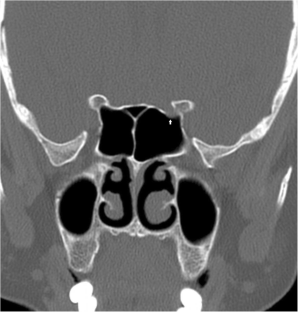

Fig. 4